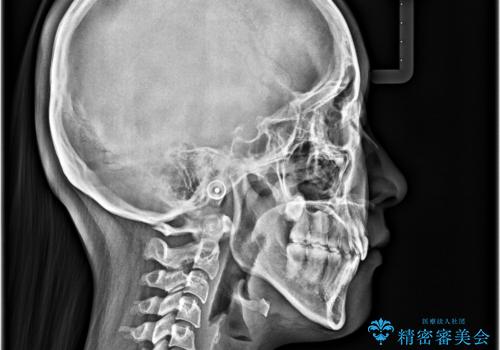

デコボコの解消で歯が磨きやすくなり、抜歯矯正により口元の突出感が大幅に改善され、スッキリした口元になりました。